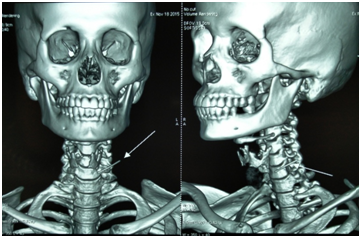

We report the case of a 40 year old female, who presented to our OPD with severe neck pain, fever and swallowing difficulty for the past one week. She had an ingestion of a sharp foreign body eight days back after which she developed pain and difficulty in swallowing. She was advised an x-ray AP and lateral view of neck, which showed a radio-opaque foreign body at the C5 and C6 level on the left side (Figure 1). A video laryngoscopic examination was normal. The patient had persistent pain and difficulty in swallowing and developed fever. She was then referred to our centre for further management.

Figure 1 X-ray showing foreign body (day 1 and day 8).

The patient was admitted and the blood investigations were done. The patient was advised an x-ray neck lateral view in which we found a radio-opaque foreign body in the same level, with pre-vertebral soft tissue widening and bamboo stick appearance (straightening of the cervical vertebra) (Figure 2).